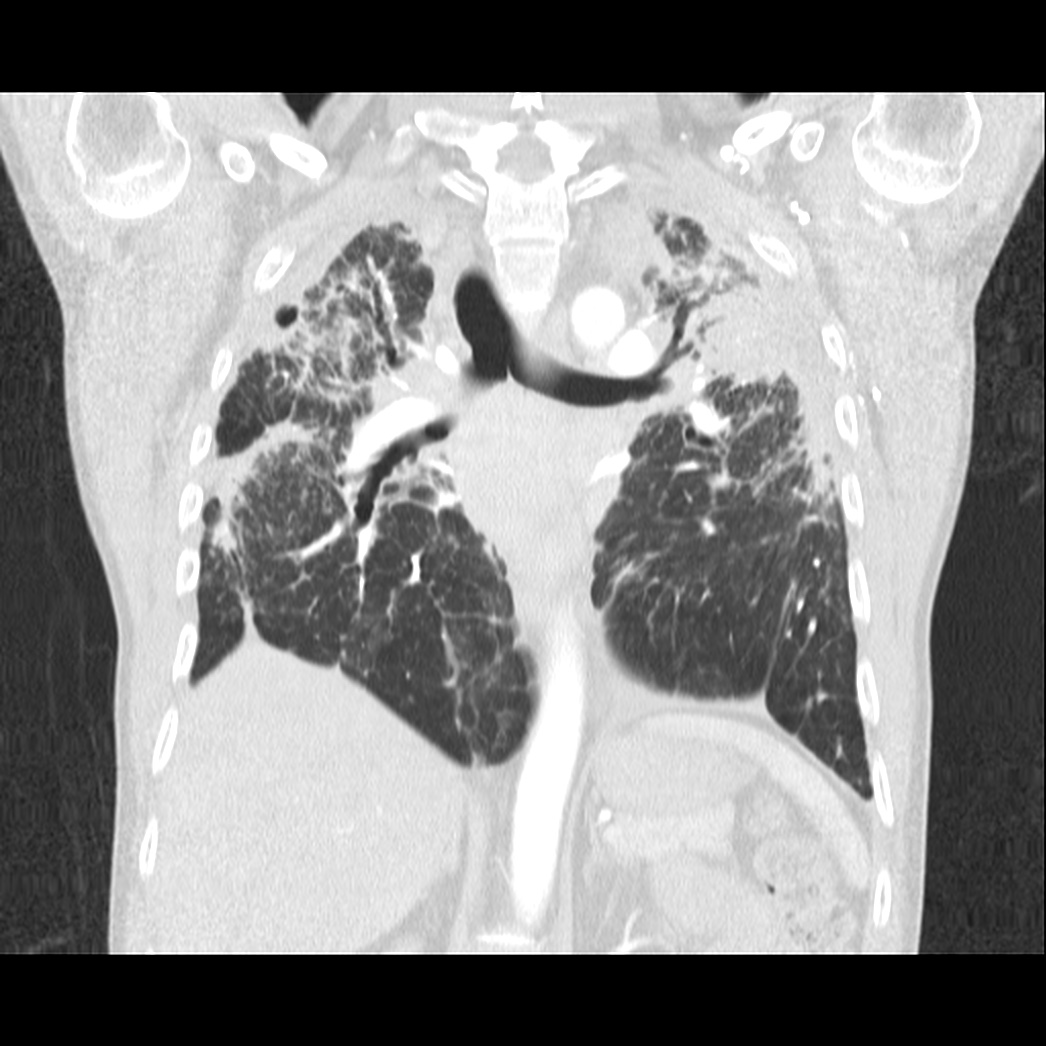

Caso neurorradiología

Paciente de 60 años con cuadro de 1 semana de evolución consistente en tropiezos frecuentes y alteración en la movilidad del miembro

inferior derecho. No refiere

cefalea u otros síntomas asociados, no pérdida de peso, no náuseas o emesis, no

sudoración nocturna. Antecedentes de hipertensión arterial y diabetes.

Escanografía